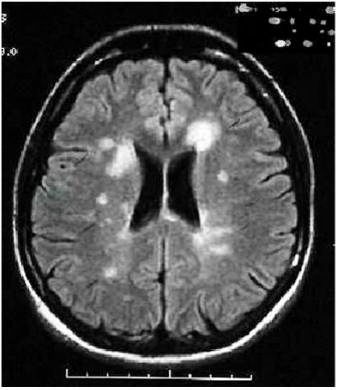

敏感性高,能检出MS患者的亚临床病灶。典型的病灶主要分布在脑室周围、胼胝体、紧贴皮质的弓状纤维处、脑干、小脑和脊髓(图1、图2)。病灶通常较小(直径3~10mm),呈圆形或椭圆形。侧脑室周围的病灶其长轴常垂直于侧脑室表面,被称为“Dawson finger征”。脊髓病灶多在一侧脊髓的后部和侧面,长度不超过1个椎体节段。急性病灶均可被钆造影剂增强。每次发作常能在MRI中发现新的T2病灶或T1增强病灶,所以MRI被普遍用于疾病的监测和随访。

图1 多发性硬化患者头颅MRI示脑室周围病灶